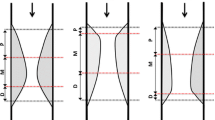

Perivascular IVUS landmarks—coronary veins, pericardium, myocardium, and side branches—were used for vessel orientation, as previously described [9]. Based on these landmarks, the vessel was divided into myocardial (inner curve of the vessel), epicardial (outer curve of the vessel), and two lateral (intermediate) quadrants. All cross-sections with eccentric plaque distribution were classified according to whether their plaque orientation was centred on the pericardial, myocardial, or either lateral side of the vessel (Fig. 1). In cases where the plaque angle exceeded 90° or the plaque was distributed in between two quadrants, the quadrant with the greater plaque thickness was selected for grouping.

Intravascular ultrasound (IVUS) images of plaque. a Landmarks for IVUS orientation. The pericardium appears as a bright and relatively thick structure with varying degrees of spokelike reverberations created by the interwoven fibrous strands. The cardiac vein was observed on the left side of left anterior descending artery. b Orientation of plaque distribution was determined by IVUS landmarks. The eccentricity index of the plaque was 3, and it was classified as myocardial plaque. c The virtual histology (VH) analysis of plaque composition was divided into four elements (fibrous area, fibro-fatty area, necrotic core, and calcified area). d This cross-section was excluded from analysis because of diagonal branching